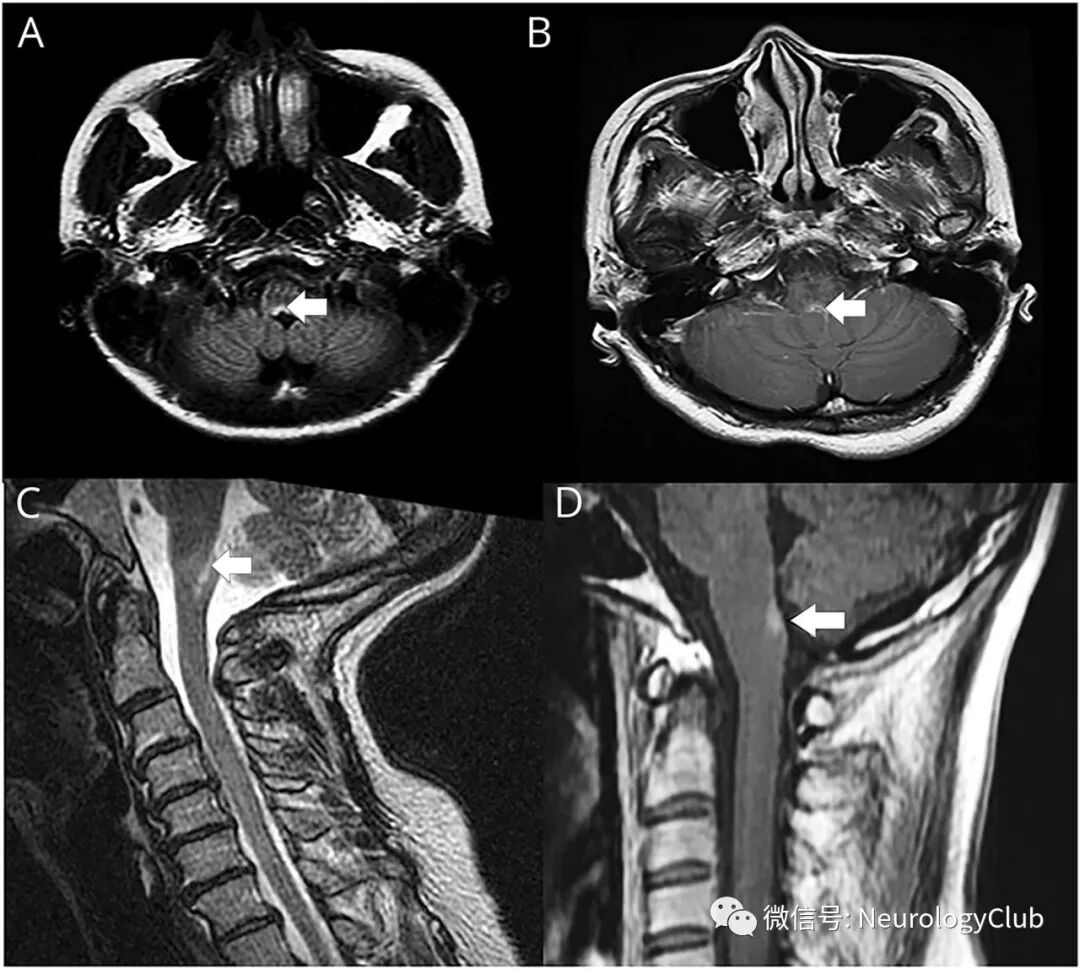

(图2:伴APS的AQP4-IgG阳性NMOSD患者的MRI表现)